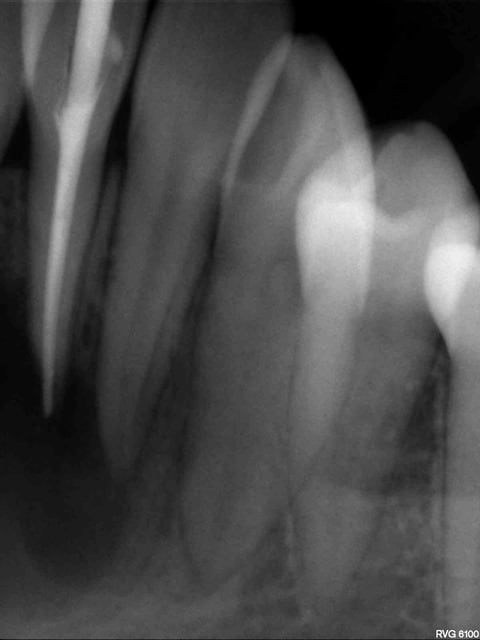

J'ai fait des rétro du bloc ant mand (la pano est sur papier donc pas terrible), les limites du kyste sont pas très nettes.

En bouche, ras, gencive normale et tout le bloc ant est positif au test au froid sauf 31. Je pense faire l'endo de la 31 et voir ensuite comment sa évolue avant de passer a la chir, ou bien vaut il mieux faire direct endo+ curetage "kyste"( qui peut être est une cavité sans épithélium)+ resection apicale. Qu'en pensez vous? Merci.

42 41 31 32 y8gtbj - Eugenol

43 42 uiuw81 - Eugenol

33 32 rd68sn - Eugenol